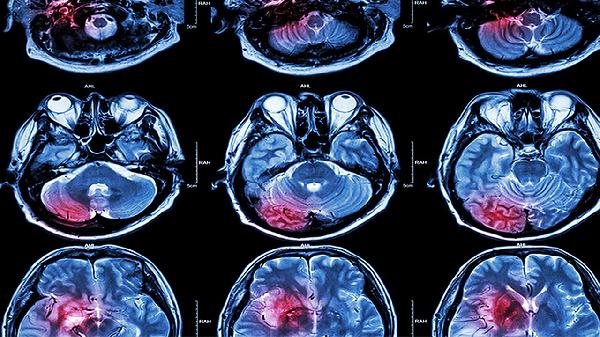

1、生理因素:语言功能与大脑的布洛卡区和韦尼克区密切相关。长期不说话会导致这些区域的神经元连接减弱,影响语言处理能力。研究表明,语言中枢的活跃度与日常使用频率成正比,缺乏刺激会导致功能退化。